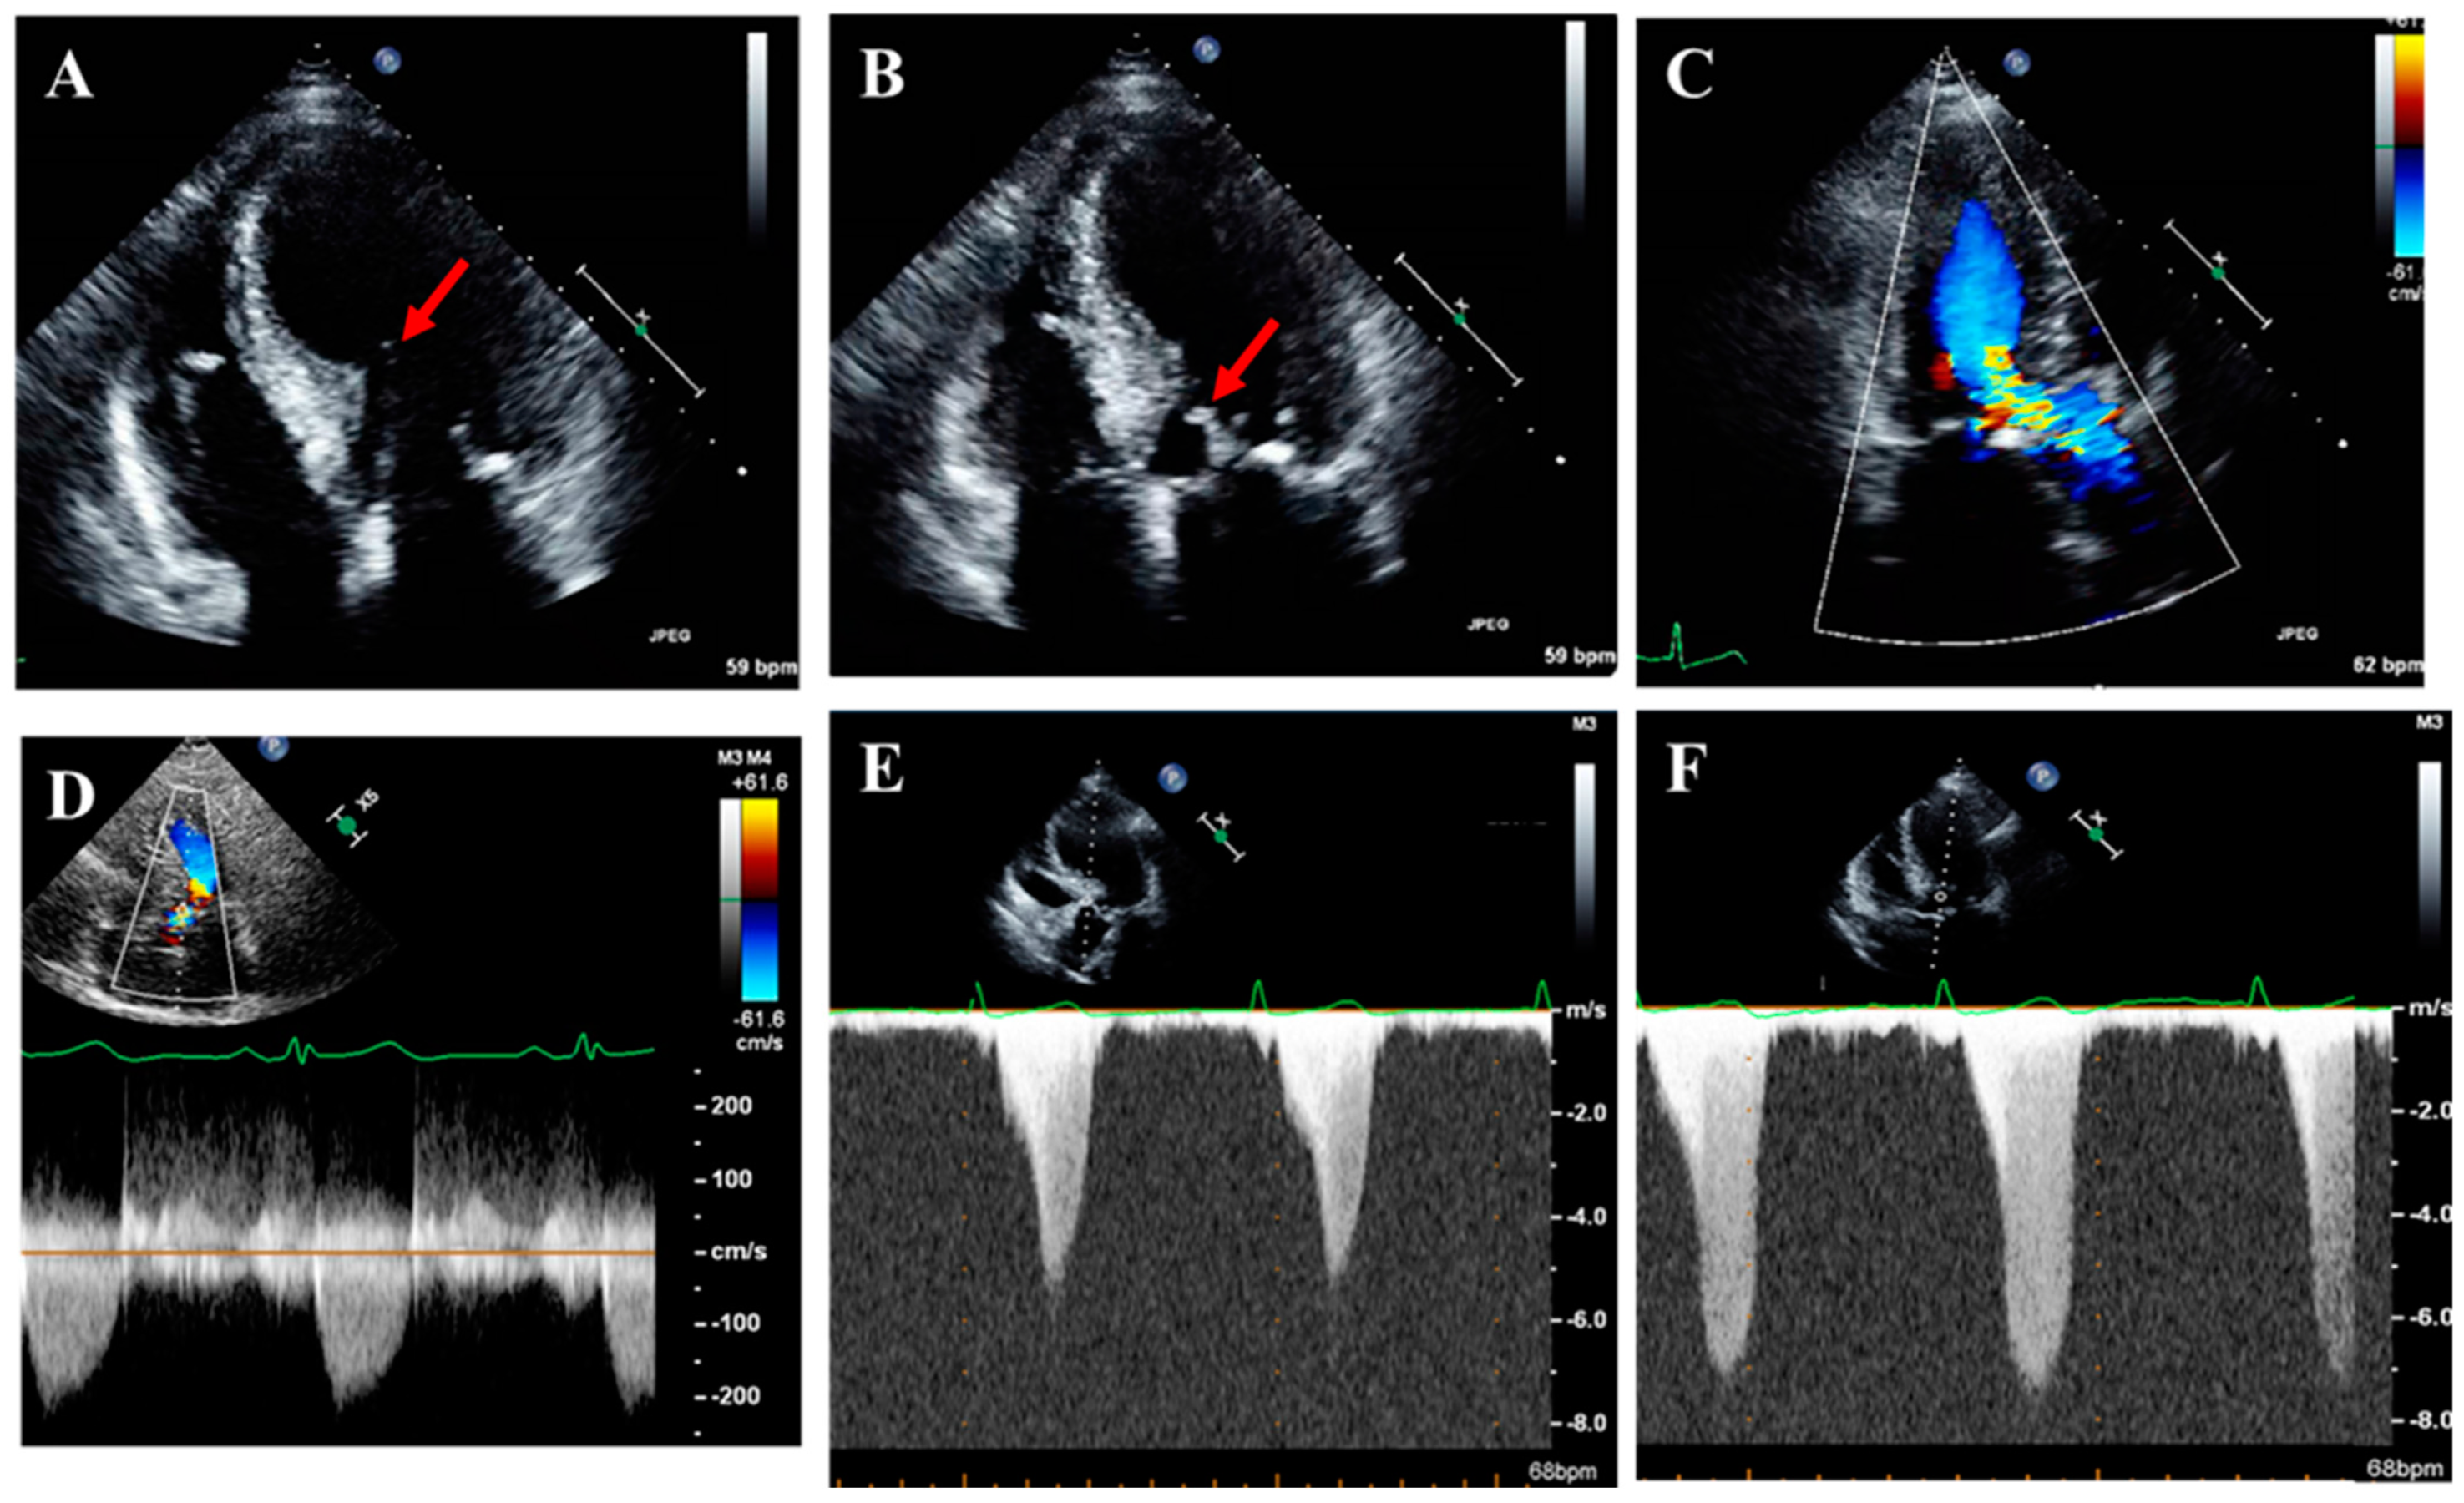

2.5. Left Ventricular Outflow Tract Obstruction

2.6. Abnormalities in Mitral Valve Apparatus and Mitral Regurgitation

3.1. Echocardiography

3.2. Stress Echocardiography